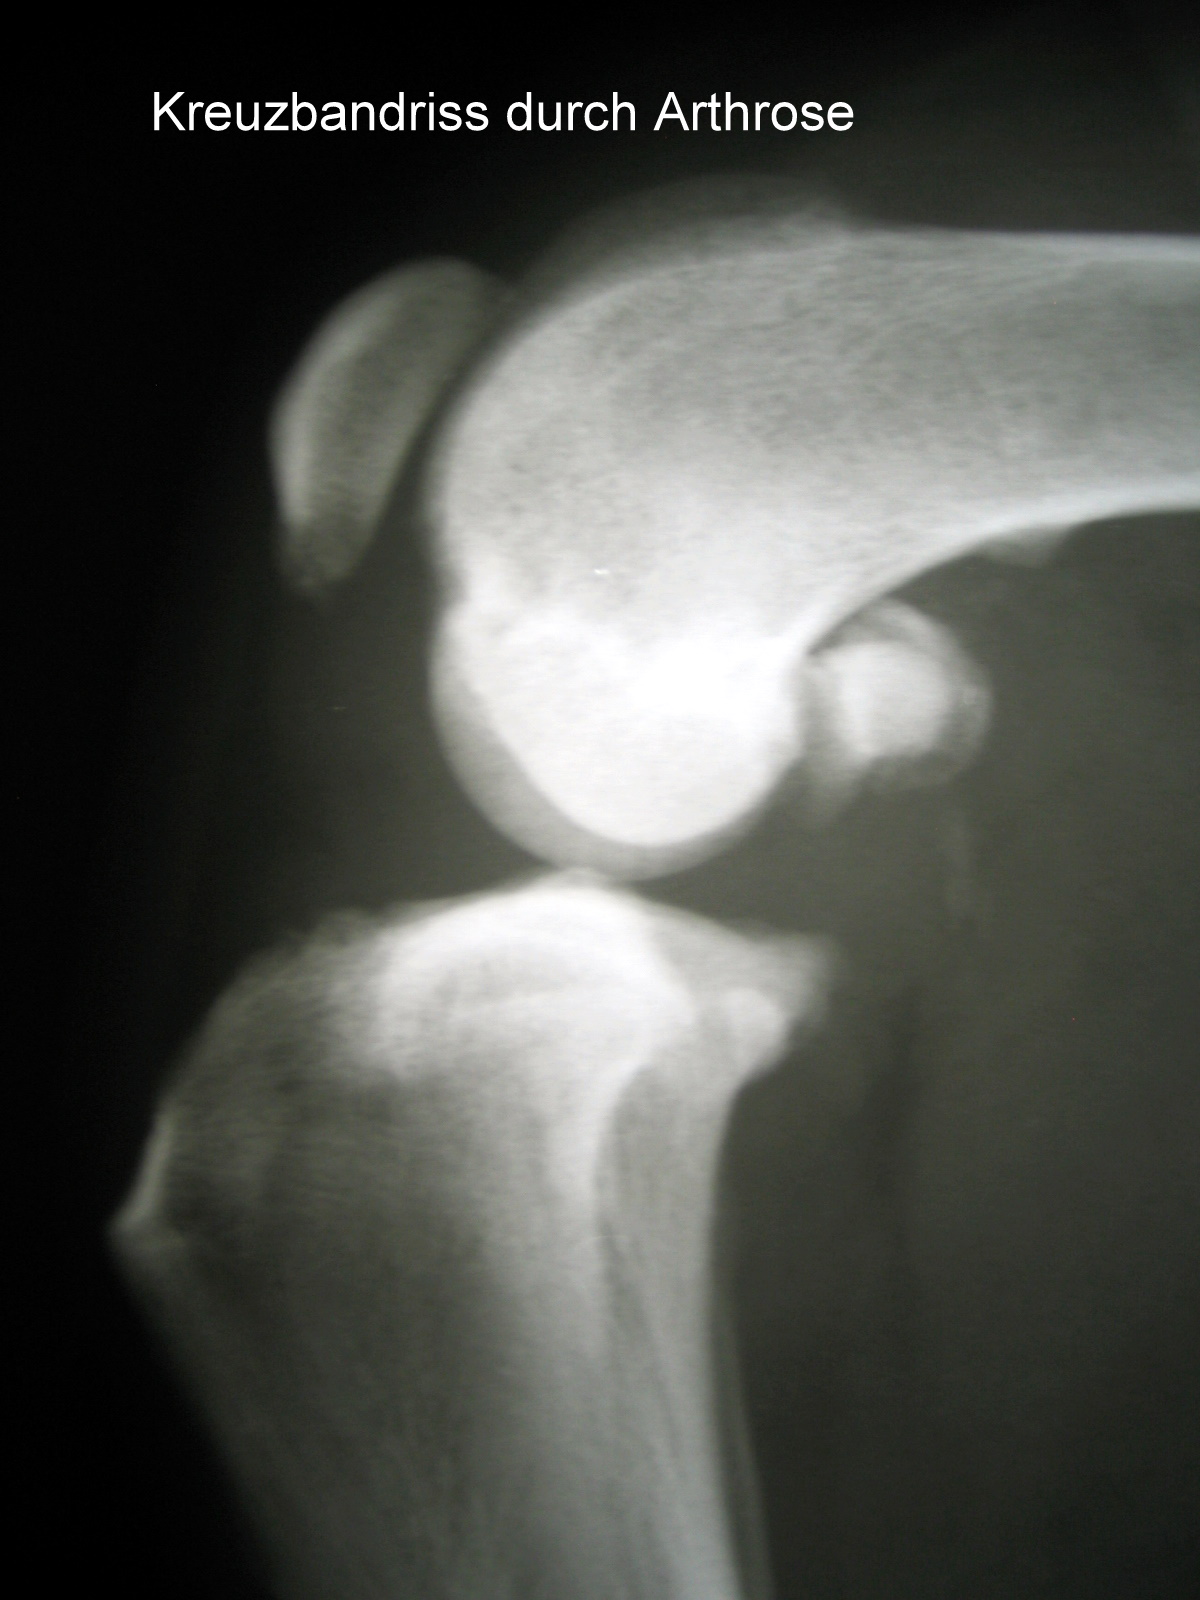

Der Kreuzbandriß beim Hund ist im Gegensatz zum Menschen in 90 % der Fälle nicht durch einen Unfall verursacht sondern eine Folge von degenerativen Prozessen im Gelenk wie z. B. einer Gelenksarthrose. Begünstigt wird diese Erkrankung z. B. durch Übergewicht. Deshalb geht der betroffene Hund meistens ohne deutlich erkennbare Ursache plötzlich lahm. Beim Neufundländer und Boxer ist eine genetische Anlage bewiesen. Generell gilt aber, dass vor allem ältere kastrierte Hündinnen (> 6-7 J) mit Übergewicht betroffen sind. Die betroffenen Tiere zeigen eine zumeist deutliche Lahmheit am betroffenen Hinterbein. Die Diagnose wird beim Tierarzt durch eine Ganganalyse, den Sitztest, eine umfassende klinische Untersuchung (z. B. Schubladenphänomen, Tibiakompressionstest) und Röntgendiagnostik gestellt. Eine Röntgenuntersuchung in mind. 2 Ebenen ist zwingend erforderlich um weitere Erkrankungen (z.B. eine Arthrose oder eine OCD) festzustellen.